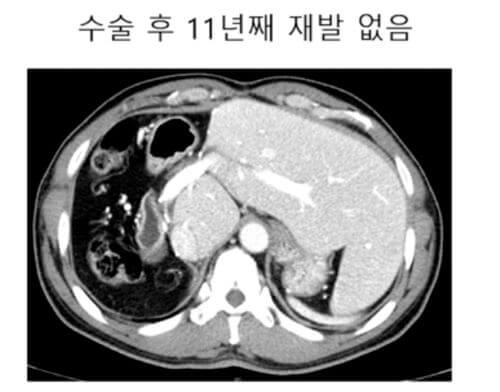

이분은 방사선 색전술이라고 하는 색전술의 하나의 방법 시술로 해서 종양이 매우 많이 줄어들고 괴사가 되고 해서 결국은 오른쪽 간을 절제하는 수술하고, 지금 7년 8년 이상 재발 없이 생존하는 분들도 있다.